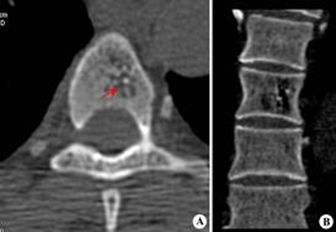

图注:左-脊柱压缩性骨折;右-注入骨水泥

1、早期:相关学者主张须经保守治疗4周后疼痛症状仍不能缓解,CT或MRI检查排除其他原因所致的疼痛方可行椎体成形术治疗。

2、近来:越来越多学者主张不需保守治疗,一旦明确诊断尽快行椎体成形术治疗,可迅速消退剧烈的腰背部疼痛,使患者在短期内即能恢复正常生活。